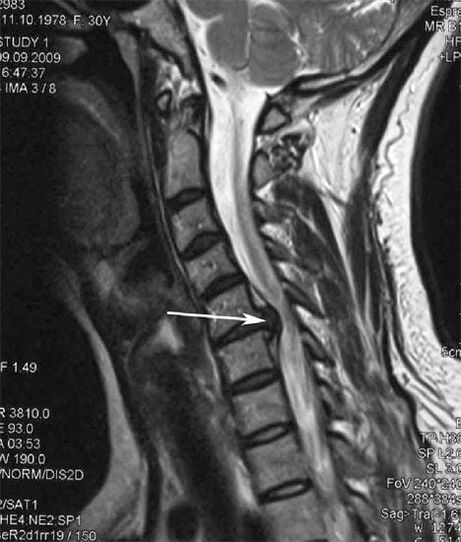

În stadiile inițiale, osteocondroza este detectată prin RMN. Ulterior, patologia poate fi diagnosticată folosind radiografie. La radiografiile coloanei cervicale, se observă o reducere a distanței dintre vertebre, modificări patologice ale articulațiilor fațetelor și osteofitoza.

Mulți oameni se plâng că nu își pot întoarce gâtul din cauza durerii severe atunci când ridică brusc ceva greu. Acest fenomen indică dezvoltarea unei hernie de disc. Cauza durerii în spate, gât și membrele superioare este ciupirea uneia dintre rădăcinile nervoase care iese din măduva spinării.